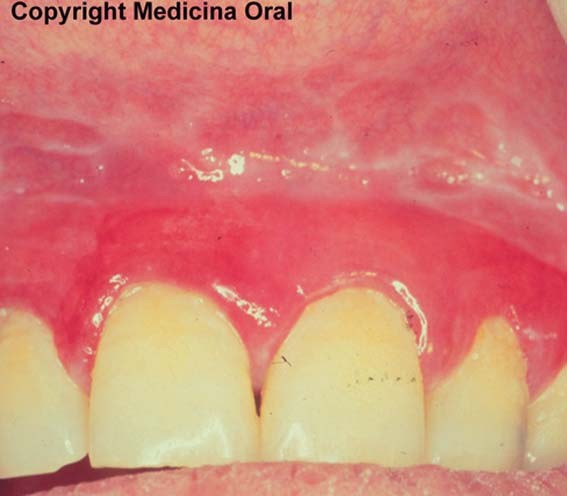

Fig. 10.6. Gingivitis descamativa por liquen |